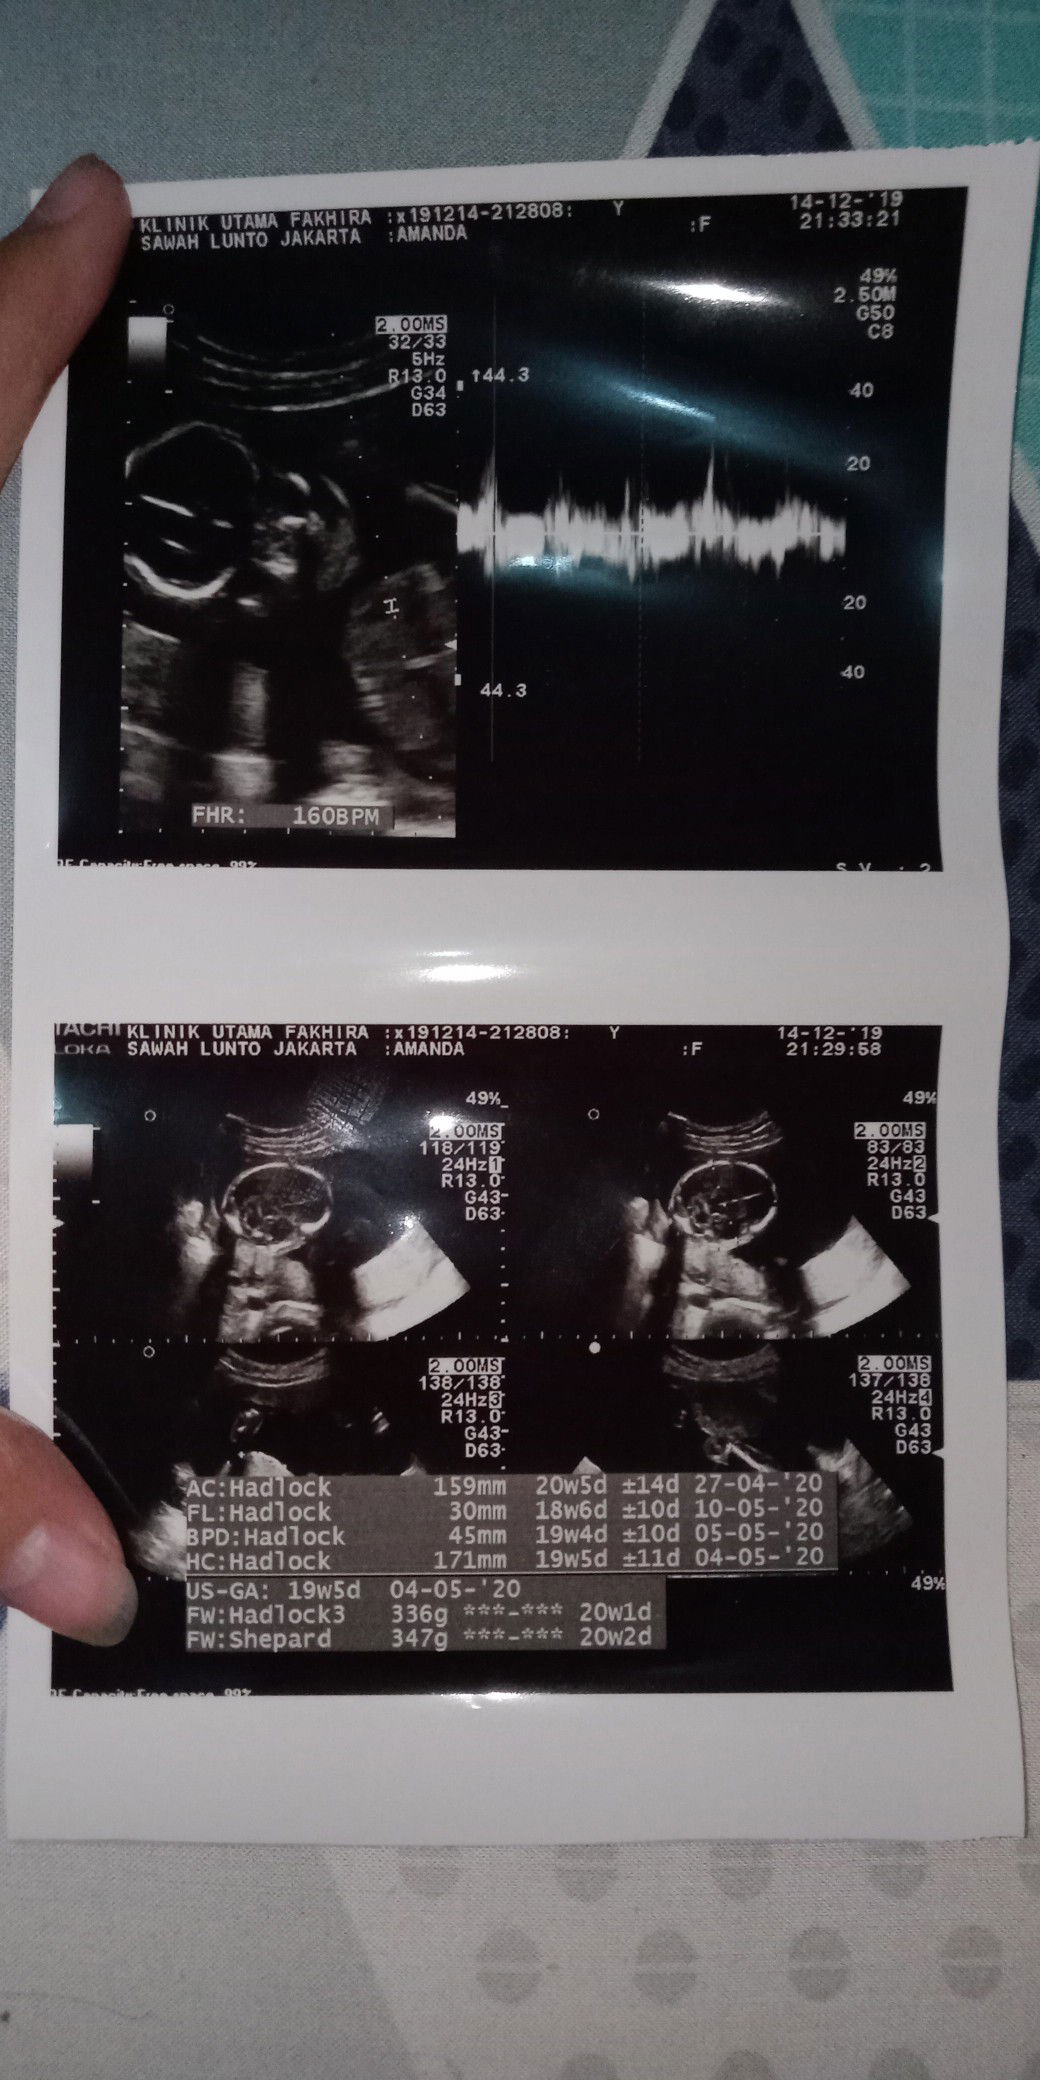

BB janin..

Siang bunda semua.. Aku mau tanya nih kira2 BB janin usia 19w normal brpa ya,semalem dokter tmpt ku USG bilang BB janin ku 360gram tp dia bilang kurang krna seharusnya sudah 500gram.. Sedangkan aku searching di google itu normal nya 19mingu 300gram.. gimana tuh Bun? Apa dokternya salah bilang ya???